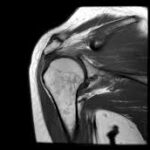

What is MRI Bilateral Shoulder?

MRI Bilateral Shoulder is a non-surgical scan method that uses strong magnets and radio signals to produce clear pictures of both shoulders. It is important for identifying different issues such as:

This scan method does not use radiation and gives important information about shoulder health.